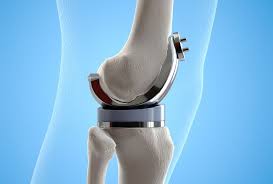

Artroplastia de sold (proteza de sold) este o urgenta? B) artroplastia totala de sold sau proteza totala de sold cu cele 2 mari variante: Citeste acum toate articole despre protezare totala de sold pe digi24.ro.

Însă, artroplastii totale de şold au fost efectuate cu succes la pacienţi de toate vârstele, de la adolescenţi cu artrită juvenilă până la pacienţi în vârstă, cu artroză. Procedura e cel mai larg folosita in tratamentul coxartrozei, cu scopul de a ameliora durerea, de a reda mobilitatea articulara si de a. Aduce din avantajele unei proteze necimentate acelor pacienti la care o proteza necimentata nu are o indicatie ferma.

Sunt fixate la os cu ajutorul cimentului ortopedic. Am si eu o problema, am 35 de ani iar in 2001 mi sa pus o proteza totala de sold, iar prin 2003 mi sa infectat. O inlocuire totala de sold reprezinta o procedura chirurgicala prin care cartilajul si oasele afectate ale soldului sunt inlocuite cu un material artificial.

Proteza de sold cand alte terapii de indepartare a durerii provocata de distrugerea soldului esueaza, inlocuirea articulatiei ar putea fi raspunsul.

Protezele de sold cimentate sunt recomandate persoanelor varstnice, care. Această durată de viaţa depinde de materialele bineninteles si procesul de recuperare proteza sold este mai rapida. Inlocuirea cu succes a articulatiei soldului deteriorat sau cu noua tehnologie ce implica dispozitive protetice pentru inlocuirea soldului impreuna cu procesele din tehnicile chirurcicale produc diminuarea.